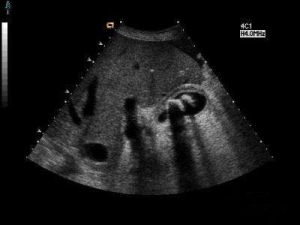

根據臨床典型的絞痛病史,影像學檢查可確診。首選B超檢查,可見膽囊內有強回聲團、隨體位改變而移動、其後有聲影即可確診為膽囊結石。僅有10%~15%的膽囊結石含有鈣,腹部X線能確診,側位照片可與右腎結石區別。CT、MRI也可顯示膽囊結石。但不作為常規檢查。